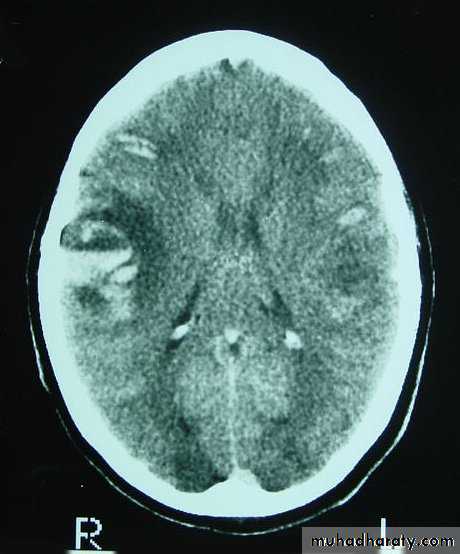

3. Brainstem and hemispheric (Cerebral) Contusion

These are areas of bruising and swellings with intact pia arachnoid, localized or generalized oedema and haemorrhage due to tearing of blood vessels.3. Cerebral Contusion

Clinical presentations:1. Prolonged periods of unconsciousness.

2. Focal neurological deficits that persist for longer than 24 hours.

CT scans demonstrates contusions as small areas of haemorrhage in the cerebral parenchyma.

Contusions may resolve with the accompanying deficits or they may persist.

3. Cerebral Contusion